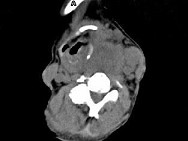

- 单项选择题女,64岁, 发现双甲状腺肿大1个月余,CT如图所示, 最可能的诊断是 ( )

A、结节性甲状腺肿

B、甲状腺腺瘤

C、甲状腺癌并淋巴结转移

D、甲状腺转移瘤

E、甲状腺结核